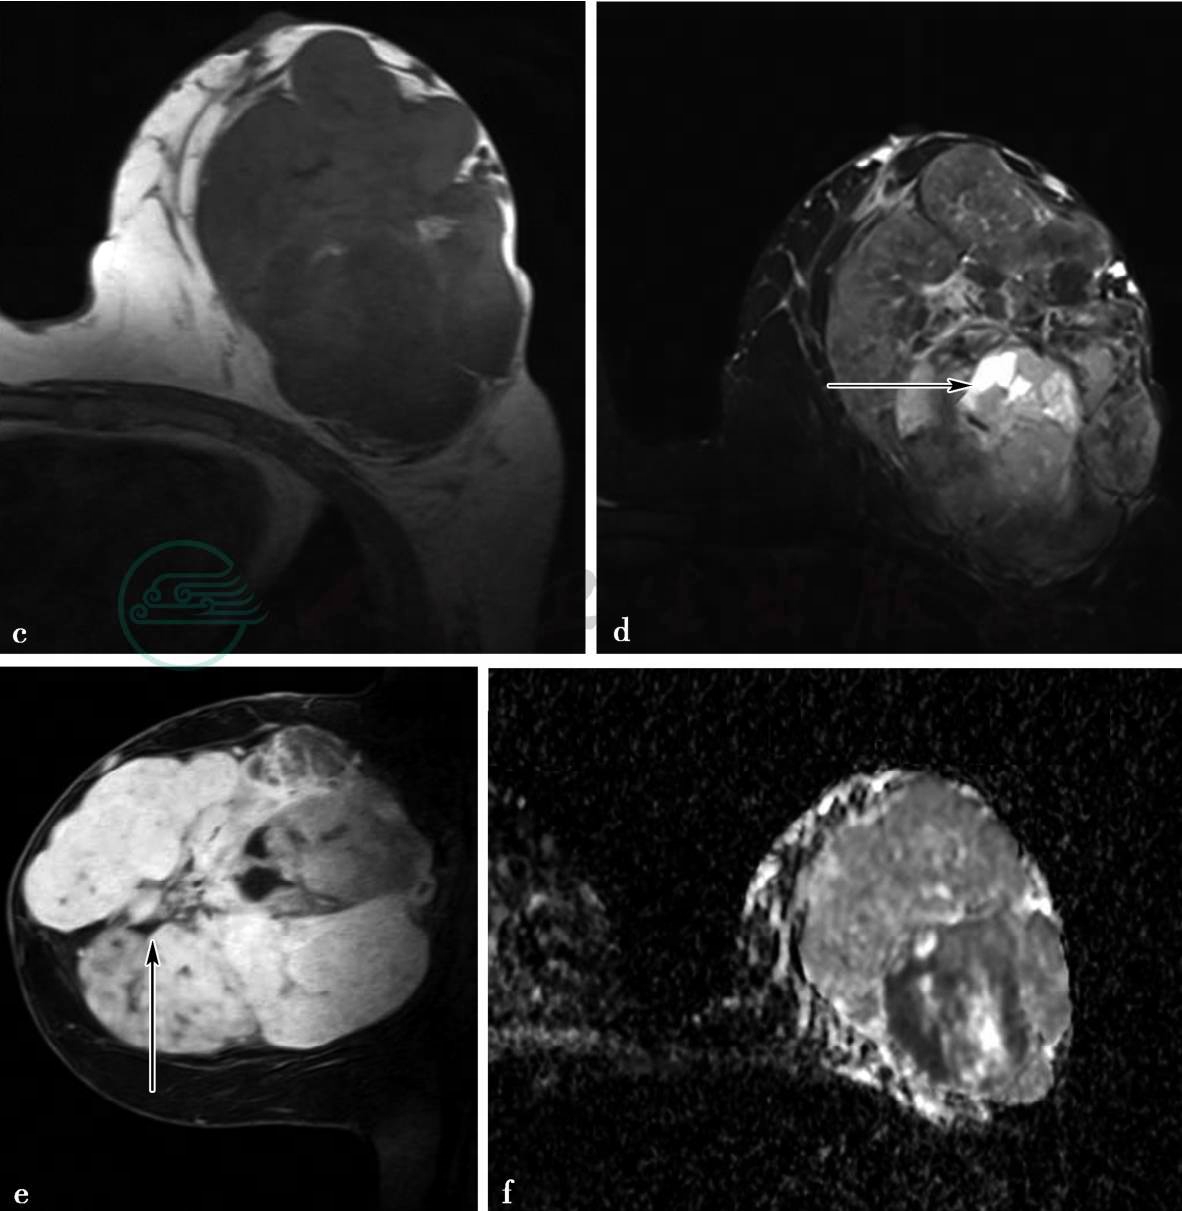

X线及MRI平扫、增强扫描

图3 图3a,X线影像内外斜位(MLO位),图3b,X线影像头尾位(CC位)。图3a,X线显示左乳巨大分叶状肿块,界清,密度增高且不均匀,未见恶性钙化,周围血管影增多,左腋区淋巴结增大。图3c~g,MRI检查。图3c,横断面T1加权成像,图3d,横断面T2加权成像,图3e,横断面增强压脂T1加权成像,图3f,ADC图,图3g,时间—信号强度曲线。MRI检查示左乳内巨大肿物,边界清,有完整包膜,分叶状,信号不均匀,内见囊状间隙(图d箭头所示)及低信号分隔(图e箭头所示),ADC值约0.83×10-3mm2/s,动态增强后囊状间隙及分隔无强化,时间—信号强度曲线呈流出型